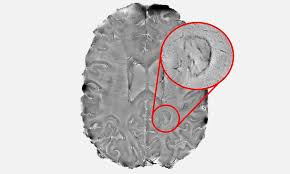

Esclerosis Multiple Wikipedia La Enciclopedia Libre

Esclerosis Multiple Wikipedia La Enciclopedia Libre from upload.wikimedia.org